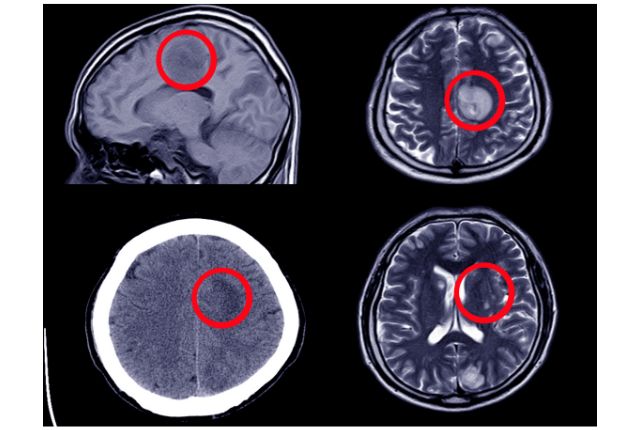

Les conséquences d’une hydrocéphalie étant incommodantes, il est nécessaire d’établir un diagnostic afin d’obtenir un traitement adapté. Le diagnostic d’une hydrocéphalie est posé après un examen d’imagerie médicale comme le scanner ou l’imagerie par résonance magnétique (IRM), notamment en cas d’hydrocéphalie triventriculaire.

En cas de suspicion d’hydrocéphalie chez le bébé, les premiers examens recommandés sont l’échographie de la tête et le scanner (ou CT-Scan), et ce, avant même d’envisager une IRM, cette dernière étant en effet habituellement prescrite aux enfants plus âgés. Chez le bébé toujours, l’hydrocéphalie peut aussi être diagnostiquée par le biais d’une échographie réalisée avant la naissance.

L'hydrocéphalie peut être diagnostiquée grâce à des examens d'imagerie médicale comme le scanner ou l'IRM.